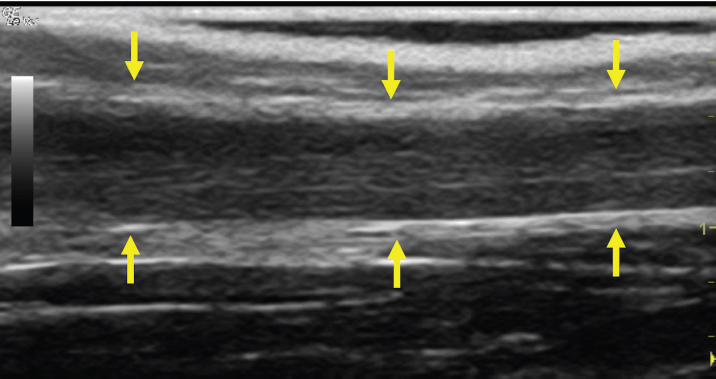

The left jugular vein appeared as an anechoic tubular structure which collapsed under the probe pressure, the color Doppler examination revealed normal blood flow within the vessel (Fig. 3). Bi-dimensional ultrasonography of the right jugular vein showed a heterogeneous, non-cavitating, hypoechoic structure occluding a narrowed right jugular vein for about 30 cm of length localized in the proximal and mid-portion of the neck compatible with a thrombus (Fig. 4). The color Doppler examination showed blood flow through the lateral portions of the thrombus in the cranial and mid-portions of the right jugular vein (Fig. 5). Cranially to the thrombus, a marked distension of the maxillary and linguofacial veins was evident, with a turbulent and echogenic flow; the latter was compatible with blood stasis near the thrombus (Fig. 6). Caudally to the thrombus, the right jugular vein presented reduced diameter, thickened walls, and normal blood flow (Fig. 7). The cranial part of the thrombus originated from a heterogeneous scare tissue, localized at the level of the right mandibular angle (Fig. 8). After injection of the first saline contrast bolus in a right facial vein, no microbubbles appeared in the right jugular vein, caudally to the thrombus, proving the presence of a complete right jugular vein occlusion. On the contrary, after injection of the second bolus, microbubbles were visualized in the left jugular vein as small, intense, echo signals within the vein lumen, demonstrating the presence of collateral circulation that drained the blood from the right facial veins to the left jugular vein (Fig. 9). Venography results confirmed the complete occlusion of the right jugular vein and the presence of submandibular venous collaterals that connected the right facial veins with the left jugular vein (Figs. 10 and 11). Based on the previous results, the diagnosis of JVT with complete occlusion of the vessel lumen was confirmed. The horse’s owner refused any proposed medical or surgical therapy.

Fig. 4. Bi-dimensional ultrasonographic image of the right jugular vein in longitudinal section. The lumen of the vessel was occluded by a heterogeneous, non-cavitating, hypoechoic structure compatible with a thrombus (arrows).ç